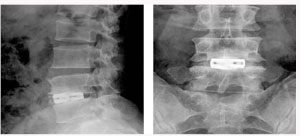

척추관 협착증의 방사선 소견

전방 요추체간 유합술 (Anterior Lumbar Interbody Fusion)

- 수술시 출혈이 적다.

- 수술 창상이 적다

- 수술 후 조기보행이 가능

- 수술 후 인접 척추체에 영향이 적다